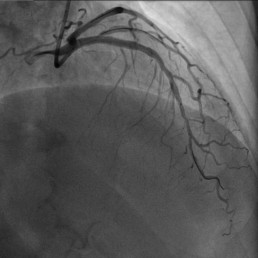

70岁的爷爷活动后,突发心前区疼痛不适,全身出汗,送入当地医院后三天内反复发作,考虑冠心病。为进一步确诊病情,转院至我院心血管内科进行治疗。

经冠脉造影检查为前降支近段重度狭窄

心血管内科为患者选择使用了2023年医院最新引进的微创技术OCT进行进一步检查,且采用ACR技术指导支架精准定位。根据ACR技术指导顺利植入一枚支架,快速完成手术,手术非常成功。